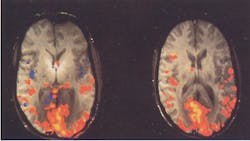

The synthesized RF pulses provide a coherent image (see the figure) compared to the first, conventionally obtained image. The scans were performed in conjunction with a GE Signa EXCITE 3 T MR Scanner. The accuracy of the DAC board provided a reference signal that compensated for the phase of off-resonance frequencies used to excite different slices.